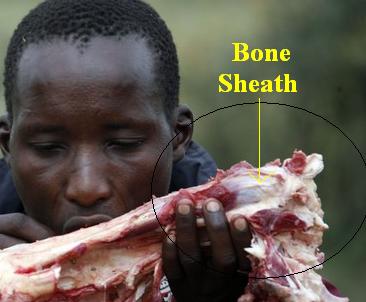

There

is one more critical issue that we cover regarding the sheaths that are

connected to the muscles and the sheaths are what are attached to the bones.

It is not the bones that raise and lower your legs or allow you to run, it is

the muscles and although bones can become inflamed it is the muscles that have

to be addressed and to be very careful that you do not do anything aggressive

join

the bone. This was in areas where there was little if any in meat.

If you are wondering what a sheath looks like, think of the bones you buy for

the dog. That white membrane to the right is the sheath and it can be

easily aggravated and in some cases damaged. Even massaging with your

hands aggressively too close to the bones where the muscle connects to the

sheath can be damaging. You want to work the muscles and improve

circulation within the muscles. If you do this, benefits will soon arrive

at the sheaths and bone.